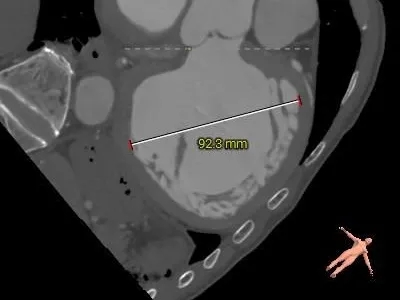

冠脉风险评估

Left Coronary 8.0mm

Right Coronary 18.7mm

LCA & Leaflet

RCA & Leaflet

Left Ventricular

-

左冠开口低,结合瓦氏窦大小,存在冠脉风险

收缩期大左室,典型关闭不全引起的心室扩张